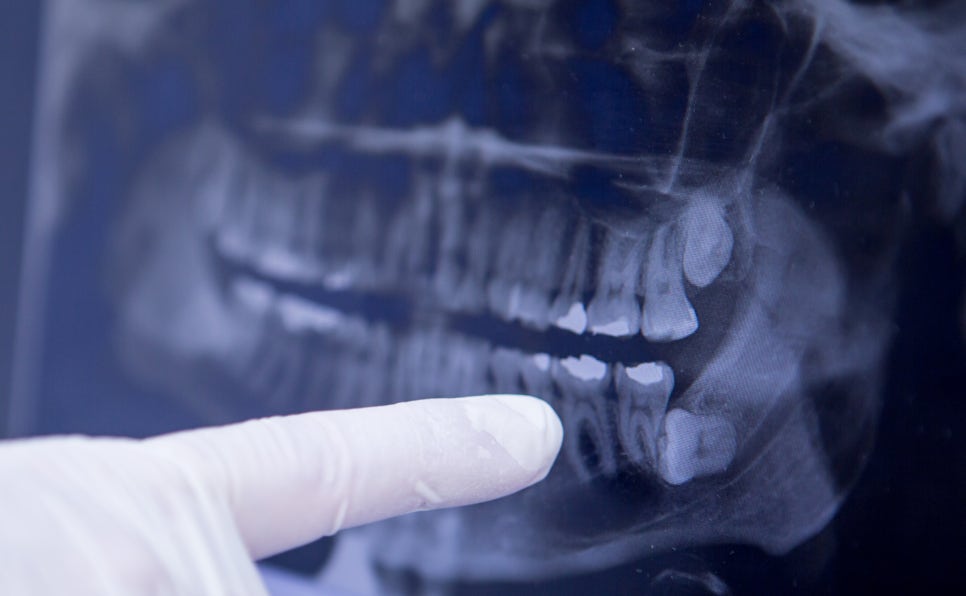

아름드리 치과 치아상식-사랑니 꼭 뽑아야 하나?

사랑니... 아픈 만큼 성숙해 지나요???

사랑니~이름은 정말 이쁜데 이 사랑니 때문에 골치 아프신 분들 많죠?

사랑니 때문에 아프기도 하고, 아프지는 않은데 뽑아야 하는 건지.. 이런저런 고민들이 생기죠..

사랑니가 정상적으로 나와서 청결하게 유지된다면 큰 문제는 없어요.

어금니 맨 안쪽 끝에 자리 잡은 사랑니의 관리가 쉽지가 않아요~ 또한 사랑니가 옆에 치아를 밀거나 옆으로 누워있거나 올바르게 나지 못한 경우는 발치를 하는 것이 좋습니다. 똑바로 나오지 못한 사랑니가 전체 치열에 영향을 줄 수 있기 때문이죠.

나의 사랑니는 어떤지... 정확하게 전문의와의 상담을 통해 사랑니를 뽑을 건지, 뽑지 않을 건지, 결정하는 것이 가장 좋은 방법입니다.